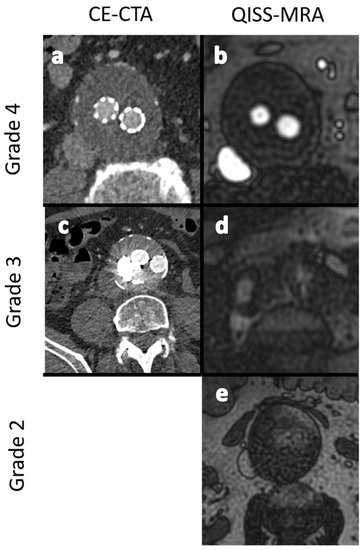

- Grade 1: Poor arterial signal and poor vascular contrast with undefinable outlining of aneurysm. Non-diagnostic.

- Grade 2: Ill-defined vessel-borders with suboptimal image quality for diagnosis.

- Grade 3: Minor inhomogeneities, and the vessel outlining is clearly visible.

- Grade 4: Excellent image without artifacts.